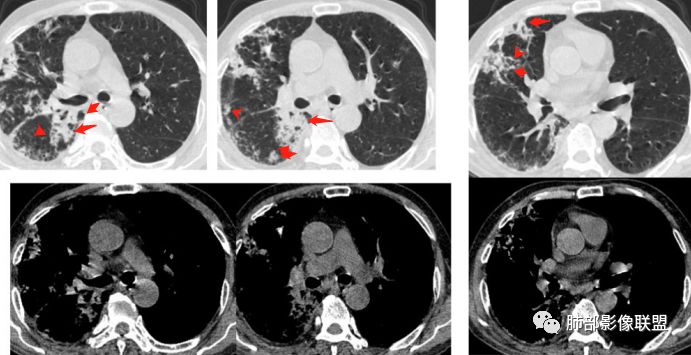

初学者:这个毛霉,壁是毛毛的,不。。。空洞壁内部不光滑的,里面丝丝拉拉的

包括曲霉,急性期也是丝丝拉拉的,但是慢性期,坏死物排空才可能光滑赶紧,这个人没有咯血。。

我慢慢给你发我手上所有的毛霉,你看。是完全不一样的。

毛霉因为嗜好血管,容易咯血,周围一般都是毛的。内壁也不会太光滑,里面也不会太干净

初学者:

随着时间。。他会慢慢变,但是内部还是那种很纤细的条索。。一般不会有乳头状突起

初学者:早期是这样的。。空洞之前。。是沿着支气管的毛玻璃。。

这种是典型的毛霉

初学者:多的我就不发了。霉菌的空洞是肯定不一样的。